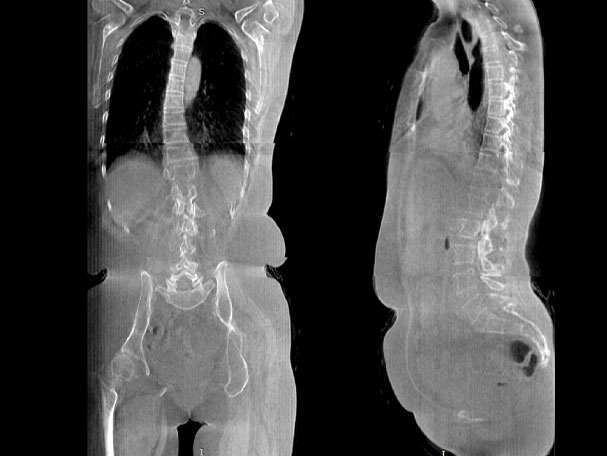

腰椎

填补常规CT/MR空白

助力术前规划和术后评估